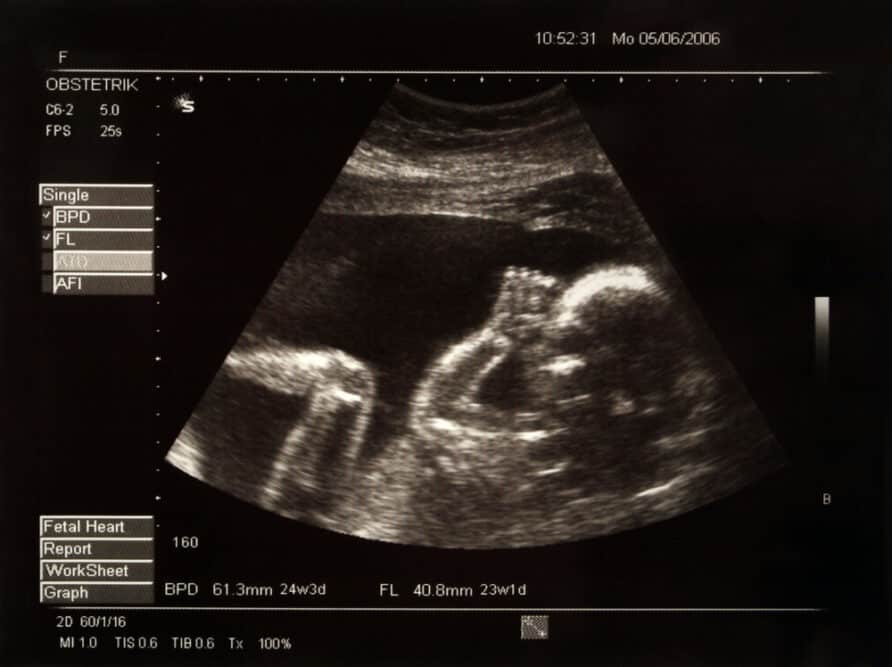

2D ultrasounds1 are the standard for checking the growth and health of a developing baby. They emit soundwaves, which bounce off of various structures within the body.

The reflected waves are then transformed into a 2-dimensional picture of your baby.

2D ultrasounds are the only ultrasounds that are able to pick up individual strands of hair. Your baby’s hair will show up as thin white lines that look like a fuzzy halo on the top of the head.

While you might have a hard time seeing it, a medically trained professional will be able to point it out for you!